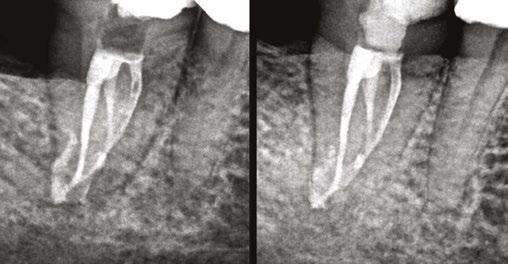

Figure 3: Second maxillary molar with external root resorption (ERR) with incidentally captured ERR on the lower mandibular first molar as well. When there is one tooth with resorption, be suspicious of other teeth with resorption, especially on younger patients Figure 6: No PARL on PA film. Clear PARL on scan taken with medicament Figures 4 and 5: 4. Mandibular molar with a J-shaped lesion due to endo — not a vertical root fracture. Path of least resistance happens to be through a distal perio pocket, but this is an endo-perio lesion and not a VRF. Incidentally, a mucous retention cyst was captured in the sinus. 5. Healing after bridge removal and retreatment

a realistic prognosis. Unfortunately, not all teeth can be saved. Some are not candidates for retreatment (Figure 11). Without a CBCT scan, it would be easy to attempt these retreatments only to discover the true problem mid-treatment, or worse — to think I had caused one (Figures 10 and 11). This added information not only helps the practitioner, but also provides patients a higher level of confidence and trust in you.

With retreatments, maybe the root canal looks completely fine on a PA or panoramic x-ray, but the patient says that it just doesn’t feel right. A cone beam can often reveal the cause of the patient’s discomfort. This could be that the tooth was perforated, cracked or has an unfilled canal, and the patient is totally justified in feeling like something’s wrong. Or sometimes the scan will show that there is another issue on an adjacent tooth or in the patient’s sinuses (causing their discomfort). When patients sense a problem but are told that there is not one (usually based on 2D radiographs), that’s not a great feeling. Being able to show the patient the CBCT scan and say, “You were right, and here’s the issue,” improves the patient experience.